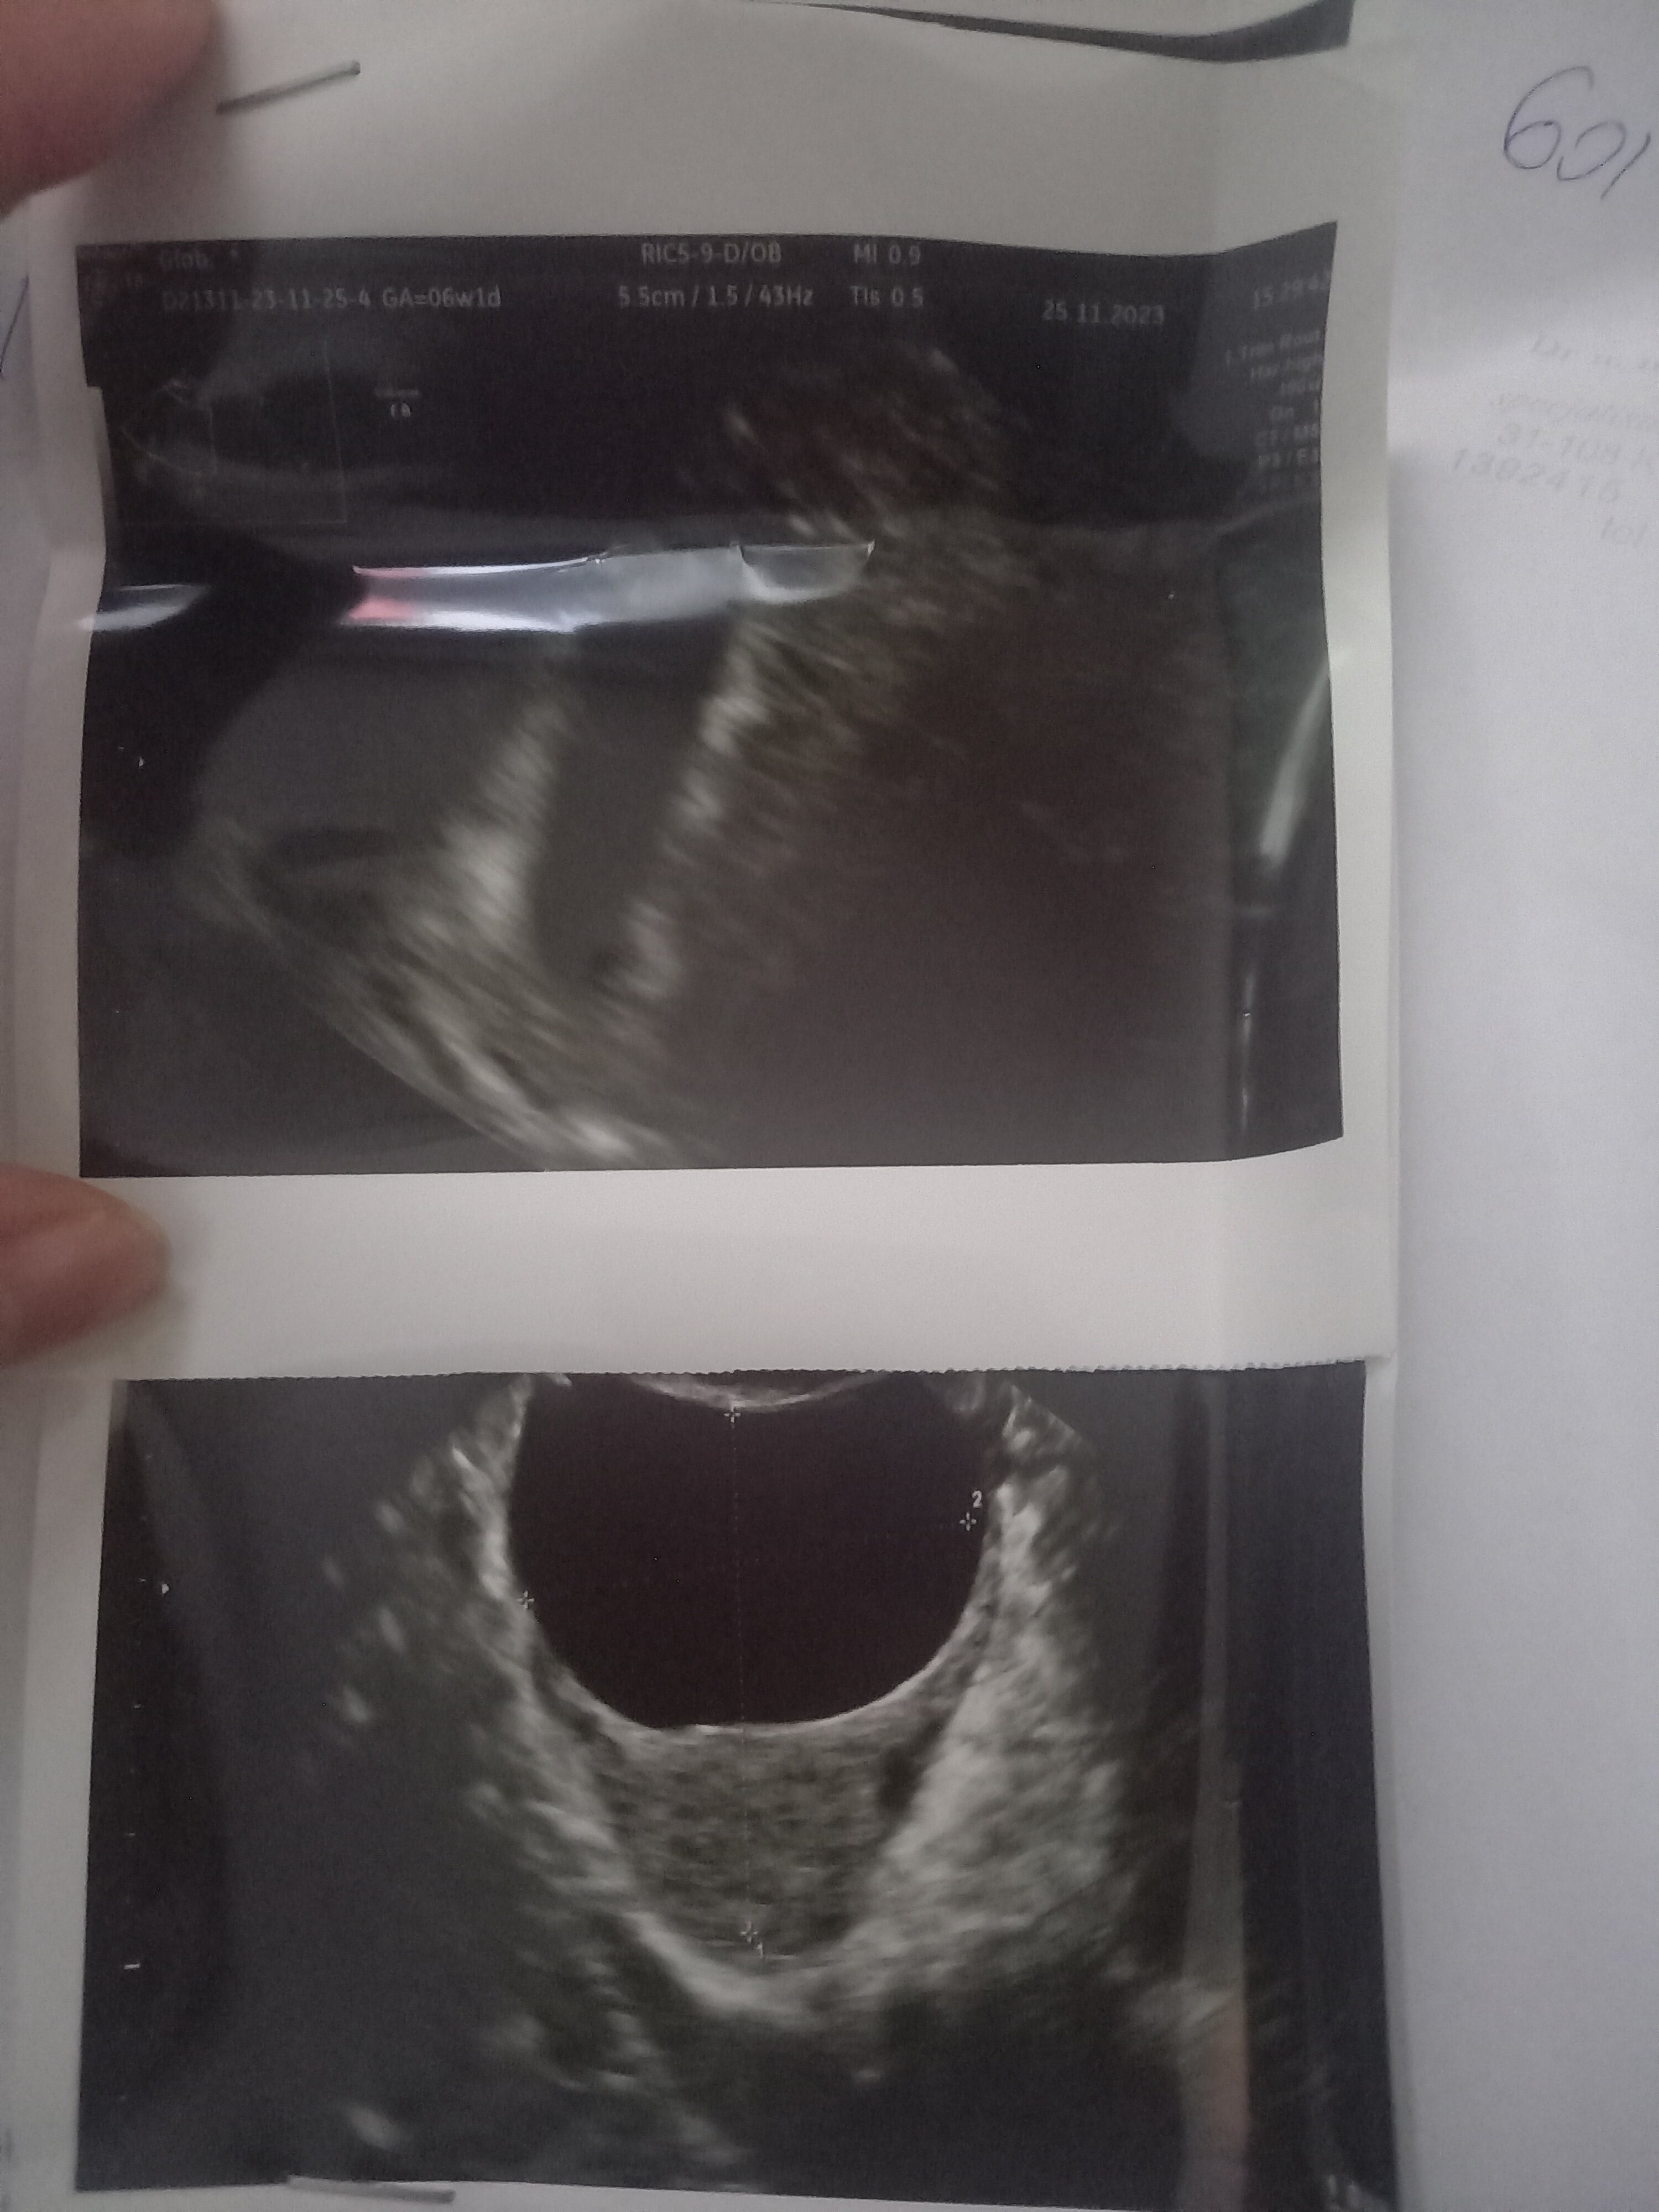

Dziewczyny pomóżcie lekarz stwierdził że to 6 tydzień a nie ma zarodka czy jest szansa ze sie jeszcze pojawi ?

Jakie są wymiary pęcherzyka ciążowego (GS) na USG?Dziewczyny pomóżcie lekarz stwierdził że to 6 tydzień a nie ma zarodka czy jest szansa ze sie jeszcze pojawi ?

Zobacz załącznik 1589561

Tu chyba nawet nie ma pęcherzyka - a przynajmniej ja go nie widz

Robiłam testy ciążowe i pozytywne a lekarz powiedział że to ciąza wewnątrzmacicznaA robiłaś betę lub test ciążowy? Brak pęcherzyka na tym etapie może oznaczać cp i trzeba go szukać poza macicą.